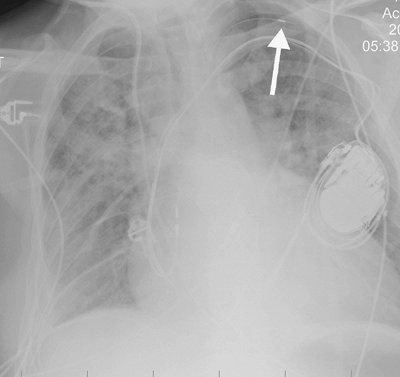

none should be present during diastole. If the catheter is short, dislodgment may occur, and the catheter may enter the right atrium, pulmonary artery, SVC, or coronary sinus. If the lead is too long, a bend in the wire may occur, causing lead fracture (Fig. 5-22). A redundant lead may also perforate the myocardium; this complication generally occurs at the time of or within a few days after insertion. The frontal or lateral radiograph will show the catheter tip outside or within 3 mm of the edge of the cardiac silhouette (Fig. 5-23). Perforation can lead to cardiac tamponade or postcardiotomy syndrome. Inflammation and infection can occur within the vein or the generator pocket; the latter occurs in up to 5% of patients (20). Major vein thrombosis and pulmonary embolism are additional complications of pacemaker insertion.

FIGURE 5-22. Looped pacer lead. PA (A) and lateral (B) chest radiographs show looping of the pacer lead over the area of the expected tricuspid valve (arrow). This positioning can result in dysrhythmia, lead fracture, or myocardial perforation.